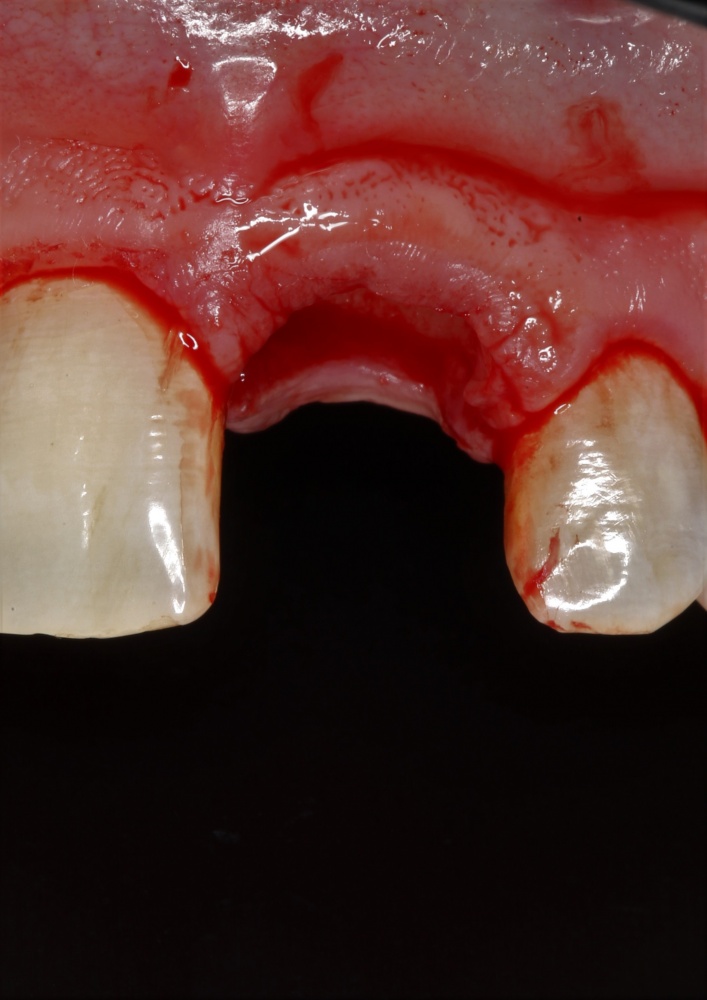

Давайте внимательно посмотрим на состояние лунок центральных резцов после удаления:

Приемлемый фенотип (сочетание толщины и ширины участка жевательной десны) — это, конечно, приятно. Но гораздо важнее сосредоточиться на рисках, их на этот момент два:

— травматическое повреждение слизистой, вызванное удаление зубов связано с тем, что при хроническом воспалении слизистая оболочка теряет эластичность, поэтому легко рвётся. Такая ситуация создаёт серьёзную угрозу эстетическому результату лечения, в зависимости от того, насколько быстро десна придёт в норму.

— как и предполагалось после КЛКТ, утрата костной стенки привела к тому, что десна провалилась в просвет лунки левого центрального резца. Это еще больше усугубляет клиническую ситуацию.